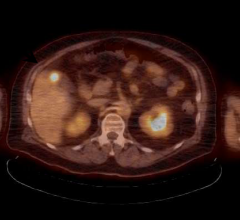

June 14, 2021 — Positron emission tomography (PET) using a 68Ga-labeled fibroblast activation protein inhibitor (FAPI) ...